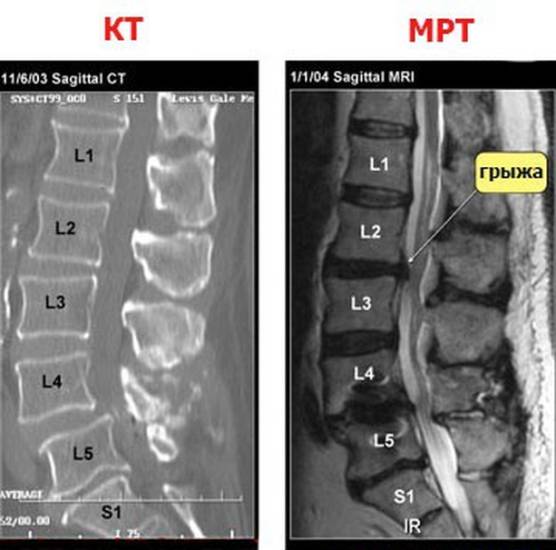

Пациентов, у которых болит спина, интересует вопрос — делать МРТ или КТ? Выбор диагностического метода остается за специалистом. Более безопасной считается магнитно-резонансная томография, так как во время исследования человек не подвергается облучению.

При острых травмах с повреждением тел позвонков рекомендуется сделать КТ, так как компьютерная диагностика лучше показывает костные ткани. Данный вид обследования применяют, если пациент не может длительное время сохранять неподвижность и при противопоказаниях к МРТ.

Когда нужно изучить состояние спинного мозга, сосудов, выявить наличие межпозвонковой грыжи, следует сделать магнитно-резонансную томографию, которая прекрасно визуализирует мягкие ткани.

В ряде случаев для изучения одной и той же области могут потребоваться сразу оба исследования.

Сравнение компьютерной и магнитно-резонансной томограмм